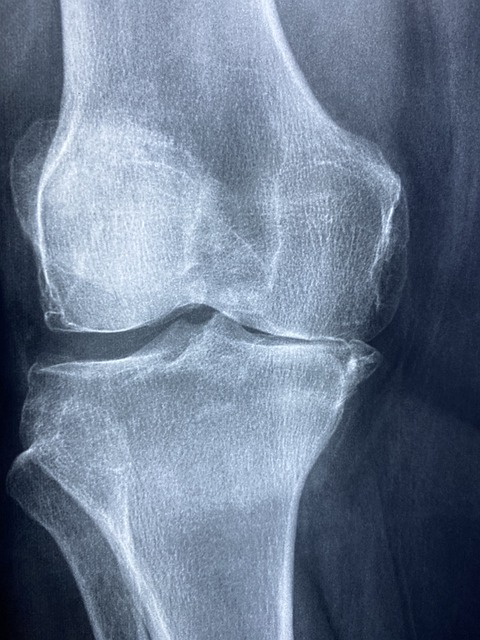

비타민 D는 칼슘 흡수를 돕기 때문에, 이 비타민이 부족하면 뼈 건강에 부정적인 영향을 미칠 수 있습니다. 뼈가 약해지면 쉽게 골절이 발생할 수 있으며, 통증이 동반될 수 있습니다.

따라서 뼈와 관절 통증이 잦으시다면, 비타민 D 부족을 고려해 보는 것이 좋습니다.